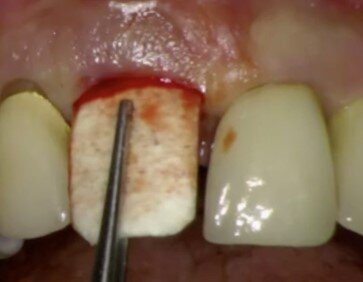

Nel caso in questione si pensò di utilizzare questa tecnica per favorire la possibilità alla paziente di avere un provvisorio immediato evitando di dovere intervenire con protesi mobili oppure andando a compromettere gli elementi adiacenti ancora ben funzionanti. La paziente venne pre-medicata con Ambramicina 250 mg (4 al dì) a partire da due giorni prima dell’intervento. Dopo aver somministrato l’anestesia locale con tecnica P-ASA6 utilizzando la Wand (Milestone) con articaina 1.200.000 l’elemento 21 veniva rimosso con molta cautela (Fig. 8). Il tessuto di granulazione presente all’apice rimosso con curettes, e l’alveolo post estrattivo disinfettato con H2O2 e Clorexidina 0.12%. La preparazione dell’intervento con conseguente carico immediato prevedeva l’uso di una mascherina chirurgica utile sia al posizionamento dell’impianto che alla successiva cementazione della corona provvisoria sull’impianto (Fig. 9). Il sito veniva preparato con le frese del caso ed era inserito un impianto Diagram (Schütz Dental) in posizione palatale (Fig. 10). Una volta inserita la fixture alla profondità e posizione corretta, con i bisturi da tunnelizazione veniva creato lo spazio vestibolarmente (laddove la frattura aveva completamente riassorbito la corticale) per l’inserzione di una lamina corticale ossea flessibile (Flex cortical sheet, Bioteck) dello spessore di 0.5 mm. La lamina veniva prima ritagliata (Fig. 11) poi idratata con soluzione fisiologica sterile per circa 30 secondi, ed infine inserita in posizione (Fig. 12).